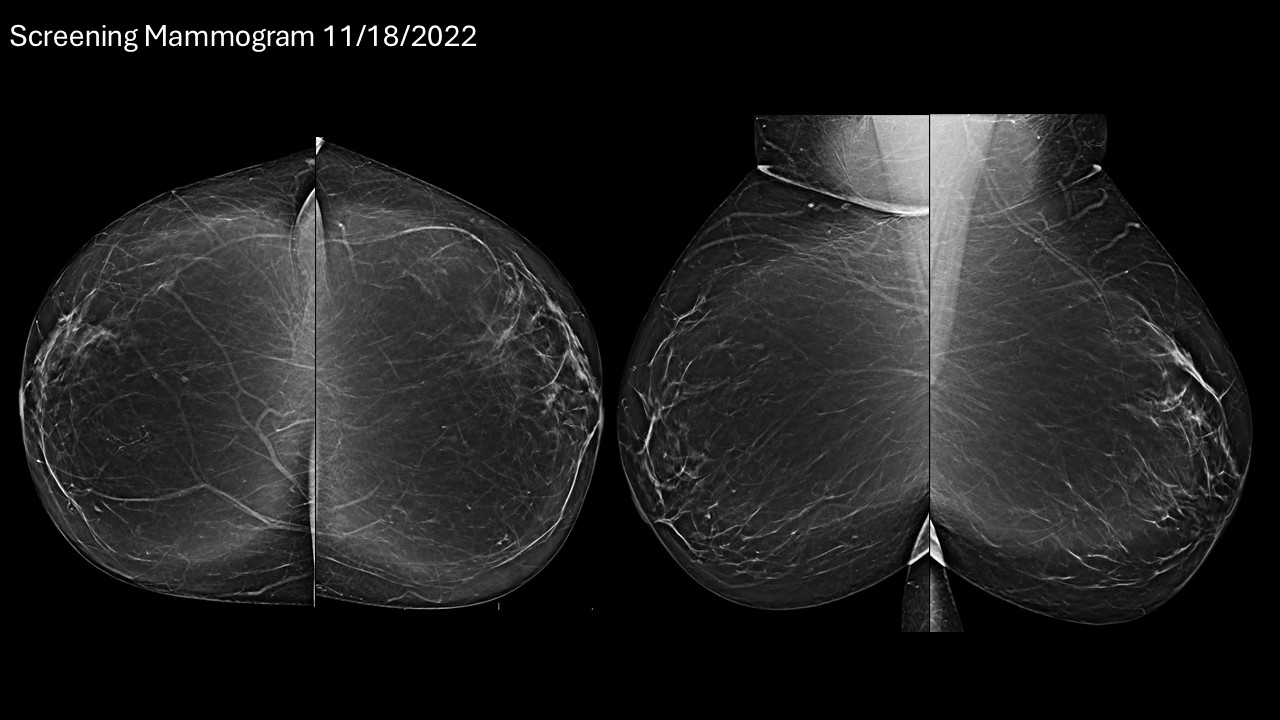

I have been working as a breast imaging radiologist for the past 3 years in Mexico City. During this time, I have had the opportunity to learn from wonderful colleagues and patients. It has been a privilege to be surrounded by such capable and dedicated people. Recently, I had also the fortune of continuing my training-which is a lifelong journey-in the breast department at Penn State Health. Penn State has an outstanding staff who put their best to make an excellent screening program. I chose to present images of a patient with an invasive ductal carcinoma detected with a screening mammogram that measured 5 mm. This patient has so far, a very successful outcome. We cannot stress enough the importance of screening in the early detection of breast cancer.